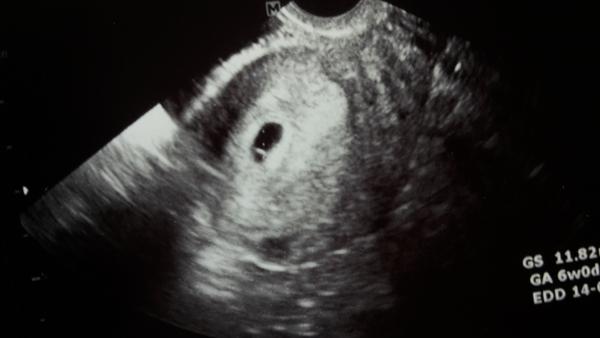

Tak se holky od včera bojim... přestalo me úplne pnout i bolet v břiše a cítím se jak úplne bez příznaků. .. Takže teplotu mam porad 37,2 ale mám strach, aby se nejednalo o zamlkle tehu :(